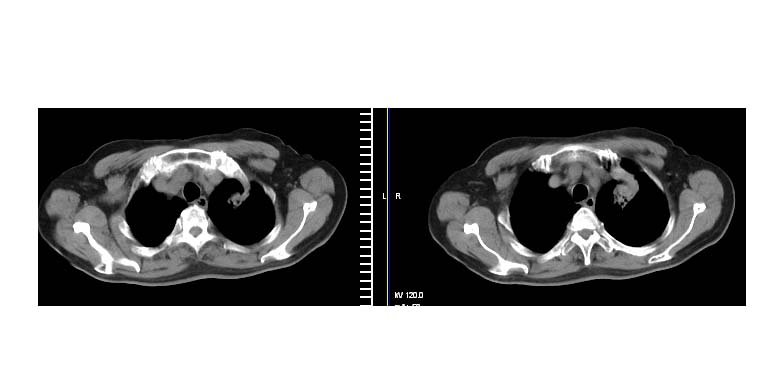

左上肺周围型肺癌伴纵隔淋巴结转移

左肺上叶尖段周围型肺癌伴左肺门淋巴结转移。

左上肺实质性肿块,浅分叶 毛糙 胸膜凹陷征 纵隔淋巴结肿大——支持:左肺上叶周围型肺癌!

左上肺软组织肿块,有分叶,短毛刺,气管旁间隙见有肿大淋巴结,考虑左上周围型肺癌伴纵隔淋巴结转移。

左肺上叶前段肺癌并纵隔淋巴结肿大。